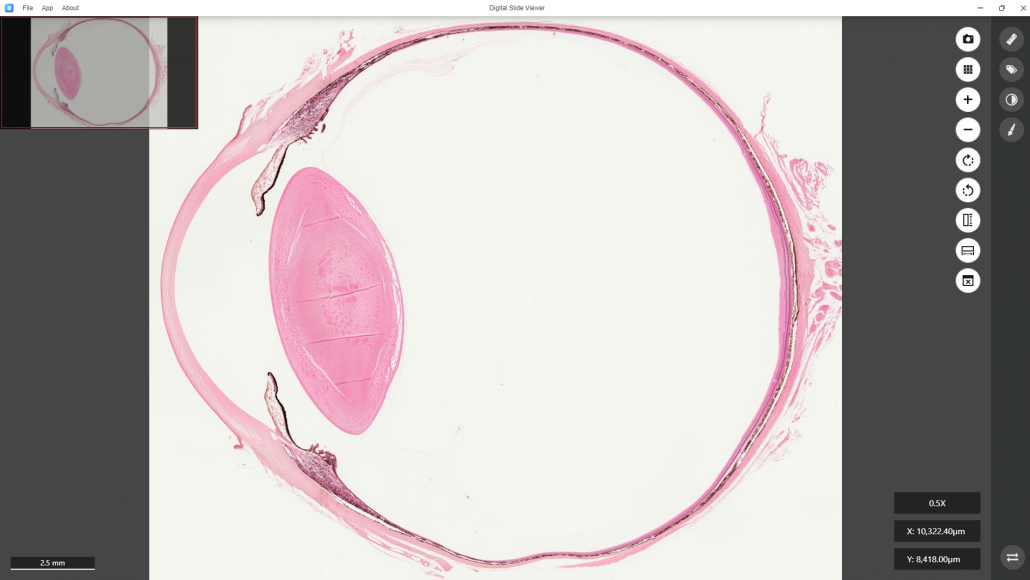

For example, here the“H130030” is selected. The DS Viewer will be initiated.

The whole section image of H130030 will be brought into the window of the DS Viewer.

This is a digitized image of a sectioned primate eye showing all must-learned layers and structures of a human-like eye.